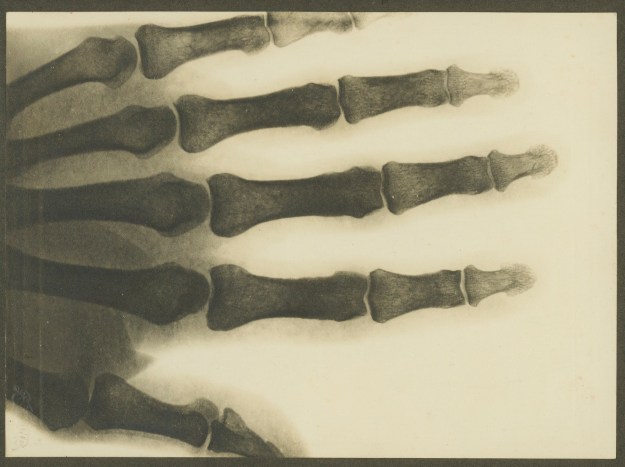

Titelbild:

Aufnahme des Ellbogens von W. H. Ying mit dem ersten Röntgenapparat am Krankenhaus Melbourne, ca. 1900-1910, Fotograf William Henry Ying;

Quelle: State Library Victoria, H84.296/12 über die National Library of Australia (https://trove.nla.gov.au/)

Am 27. Aug. 1918 wurde ich nach Sydney gesandt um meinen Arm mit Roentgen-Strahlen durchleuchten zu lassen. Ich fuhr morgens gegen 10 Uhr unter Begleitung eines Soldaten mit dem Krankenwagen nach dem Bahnhof Liverpool. Gegen 12.00 in Sydney angekommen, fuhren wir mit der Straßenbahn nach dem „Garrison Hospital“ in „Victoria Barracks“, Oxford St., Paddington, wo wir uns beim Arzt melden mußten. Die Roentgen-Aufnahme konnte nur im großen Militär-Hospital zu Randwick gemacht werden, wohin uns um 1.30 p.m. ein Ambulanz-Auto bringen sollte, so hatten wir noch Zeit, in einem Restaurant zu Mittag essen.

Um 2.00 langten wir in Randwick an und es wurden 2 Roentgen Aufnahmen gemacht, ohne daß der Verband vom Arm abgenommen wurde. Zum Garrison Hospital zurückgekommen, mußten wir uns noch einmal beim Arzt melden und gingen von da langsam zum Bahnhof, von wo wir um 5.10 nach Liverpool zurückfuhren. Vom Liverpool Bahnhof wurden wir dann im Auto zum Lager und ins Hospital zurückbefördert.

Aufnahme mit dem ersten Röntgenapparat am Krankenhaus Melbourne, ca. 1900-1910, Fotograf William Henry Wong Ying; Quelle: State Library Victoria, H84.296/11 über die National Library of Australia (https://trove.nla.gov.au/)

Am 29.8., also 2 Tage später, wurde ich wieder nach Sydney geschickt und im Garrison Hospital aufgenommen, weil sich inzwischen aus der Roentgen-Aufnahme ergeben hatte, daß der Knochen schlecht angewachsen war. Nachmittags gegen 3 Uhr wurde ich in den Krankensaal 2 (Ward 2) geführt, wo ich sogleich einen Schlafanzug, Hemd u. Halbschuhe erhielt, ein Bad nehmen mußte und mich dann zu Bett legen (Bett No. 10). Alle Zivilkleider wurden mir für die Dauer meines Aufenthalts im Lazarett abgenommen. Der Arzt Capt. Mac Innes erschien bald darauf und erklärte mir, daß ich am folgenden Tage operiert werden solle, er wolle den Knochen mit Draht zusammenbinden. Er schrieb auf meinen Krankenzettel: „fracture of right radius, X-Ray photo shows mal position of right radius and fragments“ (Bruch der rechten Speiche, X-Stahlungfotographie zeigt den Knochen in schlechter Lage u. Splitter).